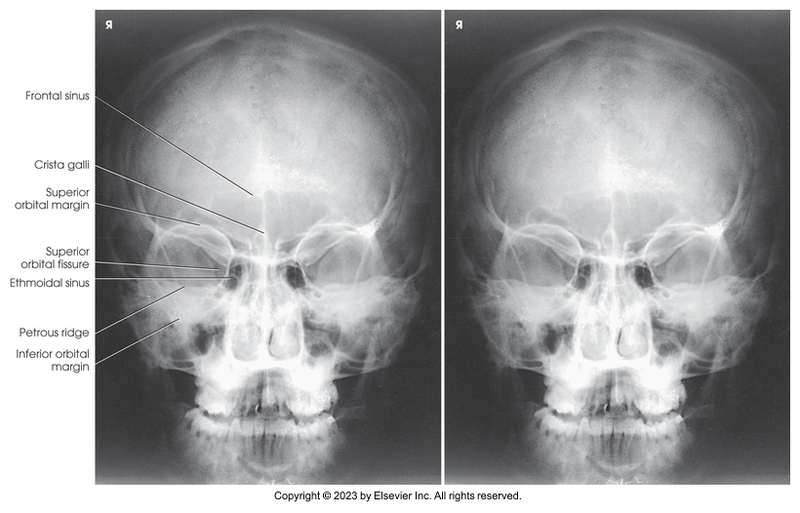

PA axial of skull - Caldwell method

PA axial skull - Caldwell Method